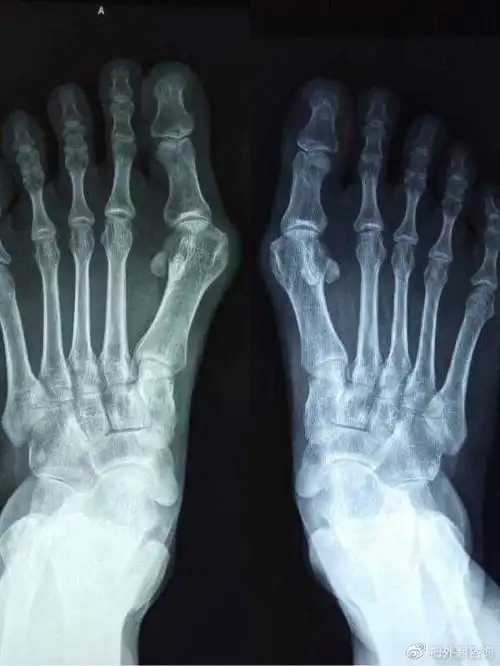

哪些办法可以缓解大脚骨疼痛简单一招穿宽松鞋子

难看疼痛穿不了鞋折磨人的大脚骨外翻该怎样治疗

大脚骨的疼痛要如何缓解,大脚骨医生和你讲一讲,看清楚

足底行走痛 原来是"大脚骨"惹的祸

大脚骨有哪些明显症状